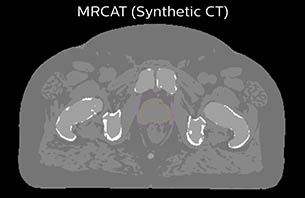

Since March 2017, clinicians in the Department of Oncology and Radiation Therapy at Turku University Hospital (Turku, Finland) have been using Philips MR-only simulation for simulating and planning radiation therapy for their patients with prostate cancer. Featuring the solution’s MRCAT approach, physicists can obtain the needed electron density information for radiotherapy dose calculations, rendering CT unnecessary in the workflow. Moreover, because co-registration of MRI and CT images is not performed in the MR-only workflow, clinicians can avoid registration errors that force margin increases, while exploiting MRI’s exceptional soft tissue visualization to delineate the prostate and organs-at-risk.

Based on the 3D T1W mDIXON images, MR-based density maps (MRCAT) are automatically generated. The VMAT (Volumetric Modulated Arc Therapy) plan is generated in TPS, based on MRCAT as primary image set. During the commissioning phase, dosimetric agreement between MRCAT-based and CT-based dose plans was studied and differences in the PTV dose were found to be minimal (<1% for most patients). Average difference in PTV mean values was 0.8% over the study group (n=62).

How does MRCAT generation work?

The Philips MRCAT approach for an MR-only based dose planning provides CT-like density information calculated from MR images for dose calculations, as well as high contrast anatomical T2W images for target delineation. [2-3] The MRCAT images with density information are DICOM conform and can be automatically exported to treatment planning systems (TPS) as primary image dataset for dose calculations and to generate MR-based digitally reconstructed radiographs (DRRs).

Electron density information is automatically generated on the MR console from a single T1W mDIXON MRI sequence in two steps: